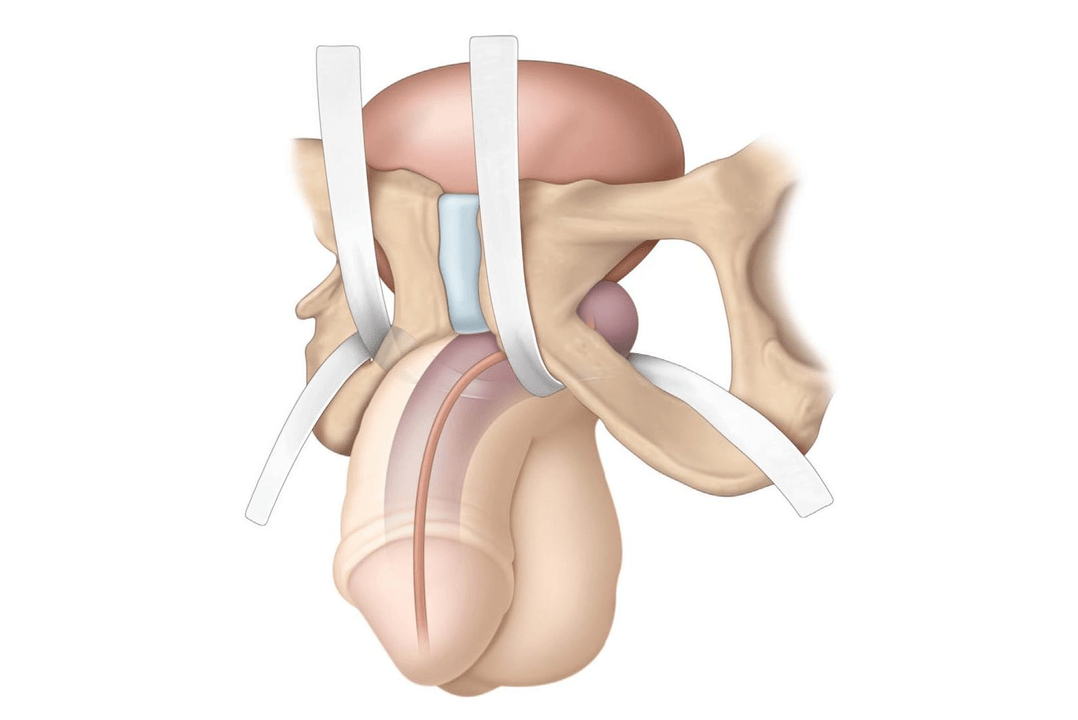

Insertion of the filler into the penis occurs in several stages:

- The groin area is treated with an antiseptic and covered with a disposable sterile diaper.

- An anesthetic gel is applied to the penis, which takes effect after 15 minutes.

- The required amount of hyaluronic acid drug is drawn into the syringe. A thin needle is inserted into the subcutaneous layer and the filler is slowly injected. The doctor ensures that the hyaluronate is distributed evenly in the injection area.

- An aseptic bandage and patches are applied to the injection site.

Methods of administration

There are several methods of inserting the filler into the head of the penis. The doctor chooses the technique according to the indications. More often, several methods are combined to improve the aesthetics of the head of the penis:

- Fan method— Hyaluronate is injected with a thin needle in different directions through a fan-type puncture.

- Point method- the injection is performed in a limited part of the penis to eliminate irregularities or deformations.

- Outline presentationThe filler is applied along the crown of the head, after which the contour becomes voluminous and more pronounced.